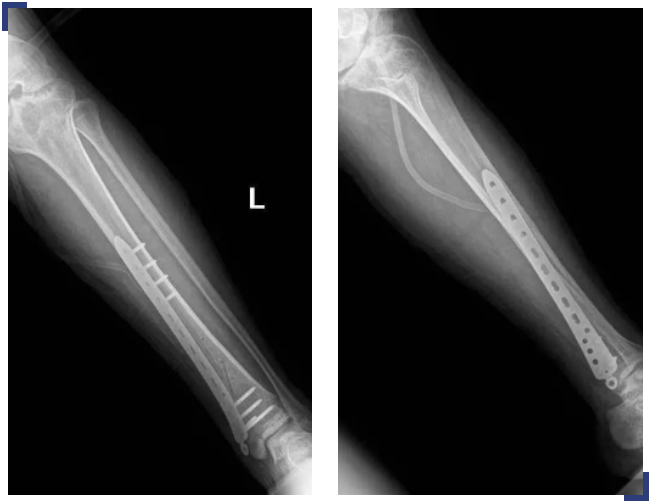

鉴于病人特殊,骨二科立即邀请血液肿瘤科(血友病治疗中心)会诊指导围术期血友病凝血因子管理。科室进行疑难病例讨论,对手术指征的把握、手术入路、固定方式、软组织的保护、如何减少术中术后出血、术后可能的并发症及如何预防等进行深入讨论。最终选择使用MIPO技术(微创钢板接骨术)对胫骨骨折进行复位,坚强固定,术前、术中、术后进行凝血因子的补充,可有效减轻软组织的损伤。术中仔细止血,减轻术后出血风险,术后早期功能锻炼。患者的右侧股骨外髁骨折无明显移位,予以保守治疗。

经过详细的术前准备,骨二科主任吴海河带领其医护团队与手术室、麻醉科、血液肿瘤内科等的密切配合,手术顺利实施,达到了理想的治疗效果,目前恢复良好。